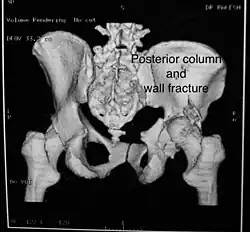

Posterior column and wall fracture as seen on 3D CT -

| Posterior column | As with posterior wall injury, this also typically occurs due to dash board injury. | Posterior column + Posterior wall | These fractures are extensions of elementary fractures. With the involvement of the posterior wall, the difficulty in treatment increases. These fractures are rarely amenable to non-surgical treatment. Due to posterior wall fracture, the hip is usually dislocated posteriorly, requiring immediate reduction of dislocation and surgical reconstruction after a few days.

The posterior column with posterior wall fracture occurs due to dashboard injury. The anteroposterior view may give clues to these injuries. Judet views and CT scans help in knowing the extent of the injury. |